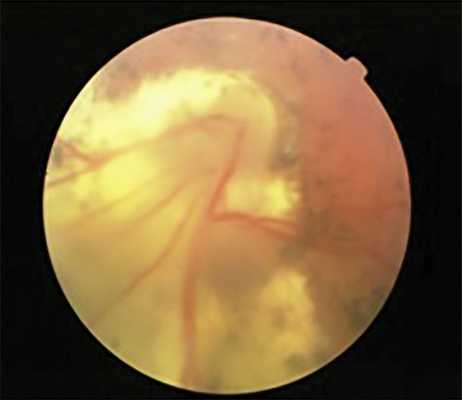

Кроме того, при самопроизвольном регрессе на 12 глазах с I—III степенью рубцовой РН в отдаленном периоде наблюдения сохранялись остаточные аваскулярные зоны на периферии сетчатки, а также анастомозы и сосудистые «щетки» на границе с аваскулярной сетчаткой, что косвенно подтверждает «незрелость» сетчатки на момент рождения. При этом, несмотря на локализацию патологического процесса в активной фазе РН в I или II зоне глазного дна, остаточные аваскулярные зоны определялись только на височной периферии, что свидетельствует о возможности продолженного васкулогенеза сетчатки уже после завершения активной фазы РН (рис. 3).

Рис. 3. Остаточные аваскулярные зоны и сосудистые анастомозы у ребенка 10 лет на глазу с рубцовой РН.

Коатсоподобные хориоретинальные очаги выявлены на двух глазах с IV степенью РН у пациентов 12 и 17 лет. Развитие этих изменений произошло в зонах интра- и преретинального фиброза и характеризовалось появлением субретинального экссудата желтоватого цвета, сосудистых мальформаций с новообразованными сосудами (рис. 6). Причины таких изменений окончательно неизвестны, возможно, их развитие связано с длительной ишемией.

Рис. 6. Коатсоподобные хориоретинальные изменения на глазу с рубцовой РН III степени.